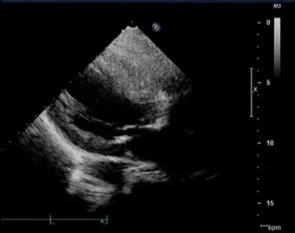

术后超声

TAVR术后床旁超声描述:主动脉瓣位生物瓣位置、形态、回声、活动正常,生物瓣功能良好,主动脉瓣峰值跨瓣压差从术前126mmHg降至7mmHg,平均跨瓣压差从术前75mmHg降至3mmHg。心功能明显改善,LVEF恢复至73%,左室壁运动正常。